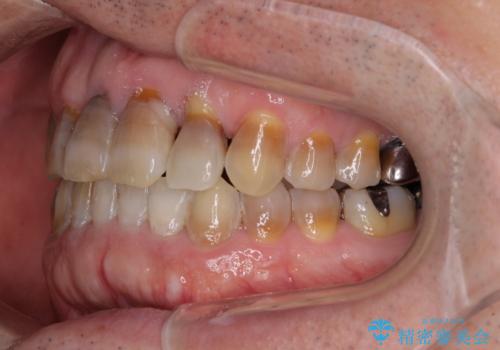

上顎の狭窄歯列 インビザラインによる拡大矯正

- 前歯の叢生と臼歯のクロスバイトを気にして来院された患者様です。

急速拡大装置による上顎の側方拡大を行い、その後はインビザラインより歯列を改善することとしました。

20代後半以降の男性は上顎骨の側方拡大処置の成功率が低く、今回も骨を拡大することができませんでした。

しかしながら、歯列を側方に拡大することができ、その後はインビザラインにて叢生を解消することができました。